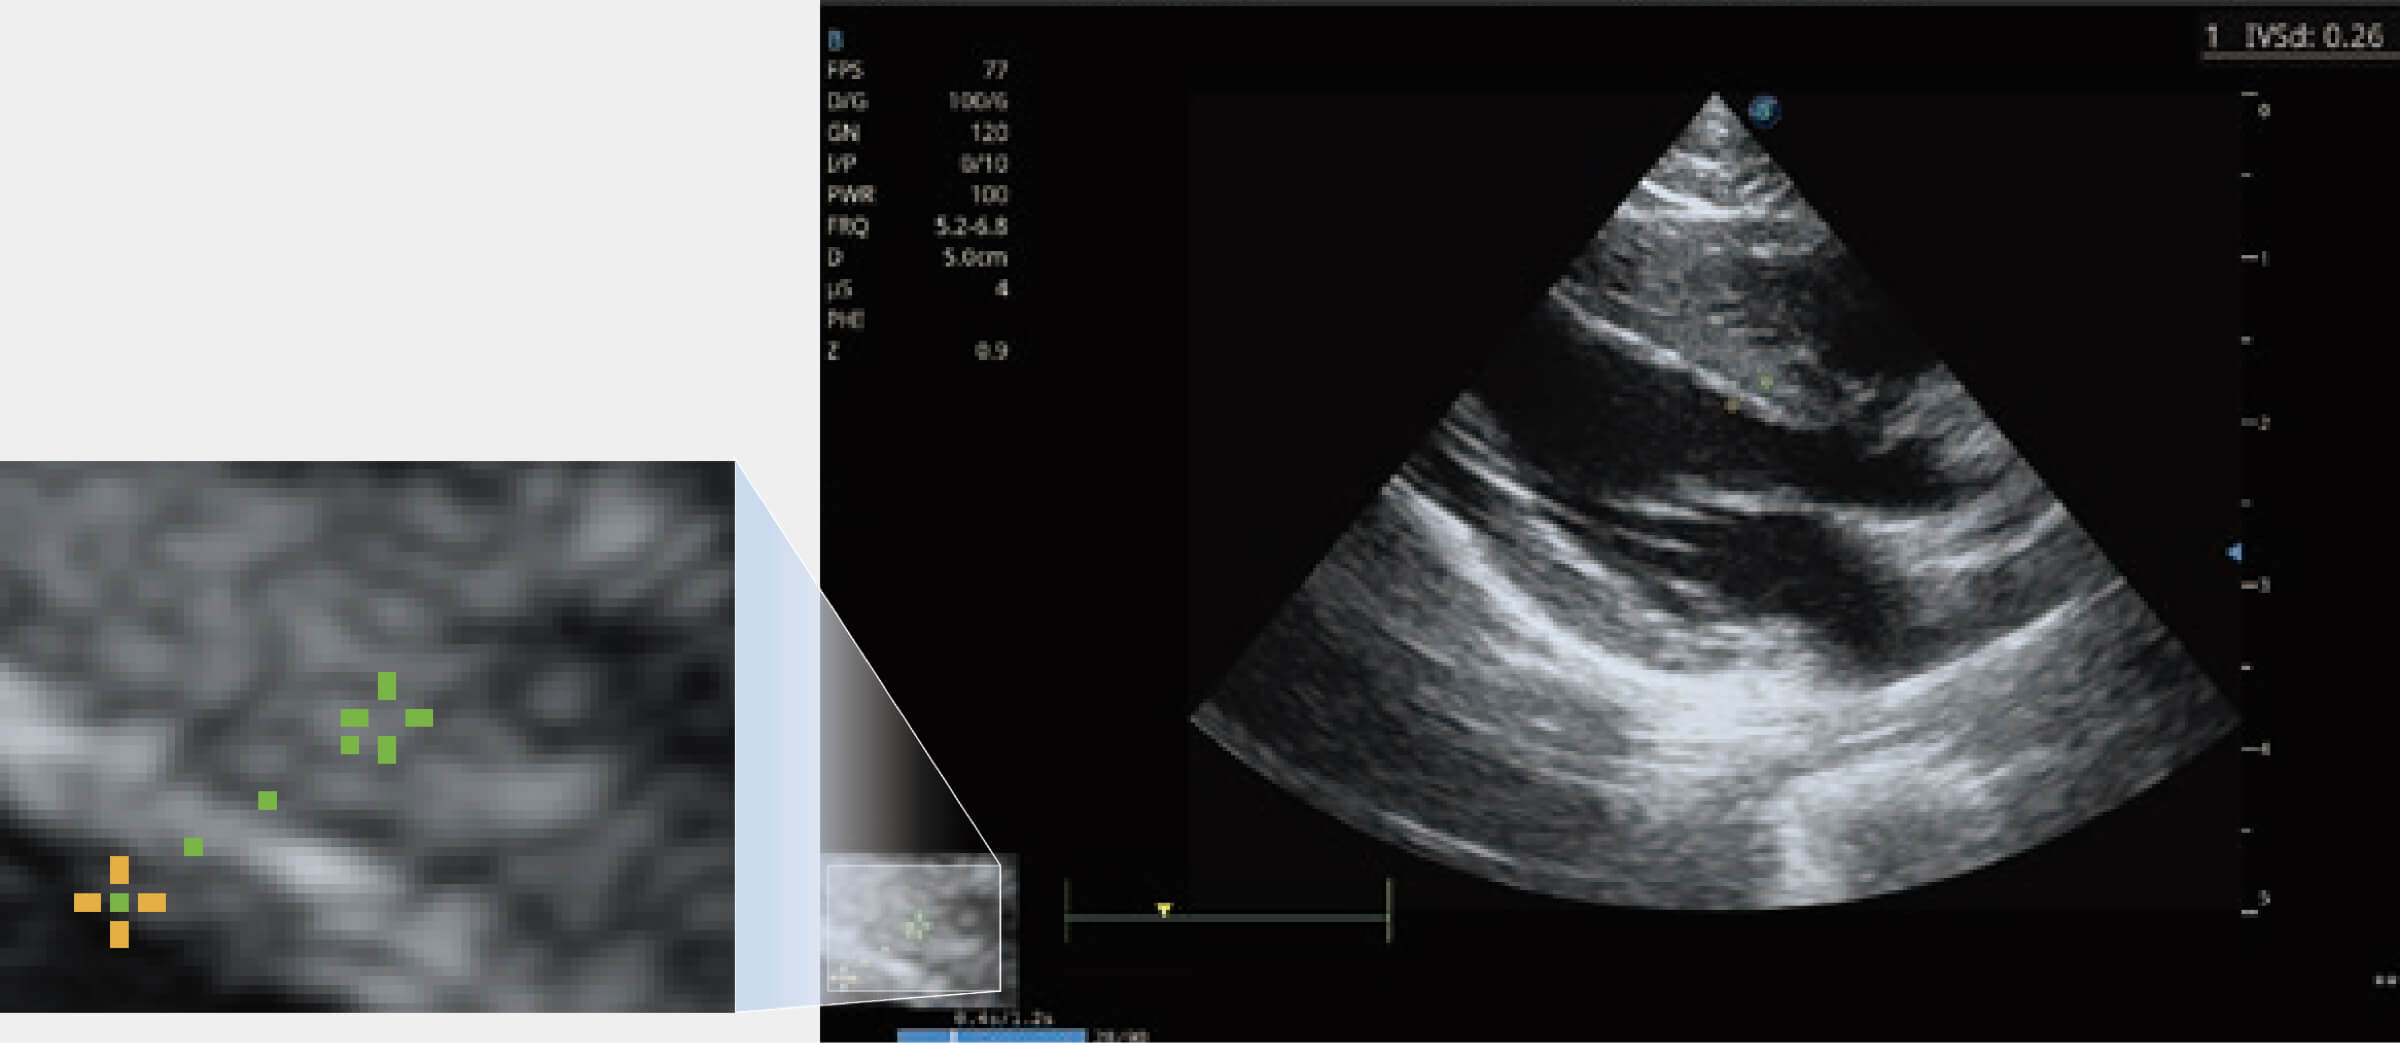

ProPet 80 配備了豐富的心臟探頭群、先進的成像技術(shù)和專業(yè)的心臟測量工具,可幫助動物醫(yī)生為不同體型和生理結(jié)構(gòu)的動物提供心臟和心肌功能的全面評估。

實時用顏色表示心肌組織運動,觀察和定量組織的運動情況,對快速檢測與評估心肌的灌注和活性、電傳導及心肌收縮和舒張功能等均能提供重要的診斷信息。

通過心肌識別技術(shù)與二維斑點追蹤技術(shù)相結(jié)合,對心臟的超聲圖像進行量化分析。計算心肌17個節(jié)段的應變、應變率、速度、位移等,并通過牛眼圖的形式進行呈現(xiàn)。

通過360度任意調(diào)節(jié)3條M型取樣線,在同一心動周期上觀察心臟不同位置的運動曲線,得到準確的心功能測量數(shù)據(jù),有效評估心肌運動及左心室功能。

能夠基于左心室壁追蹤和辛普森法,自動計算射血分數(shù),支持多個可移動點描跡,與手動測量相比,極大節(jié)省了動物醫(yī)生的時間和精力。